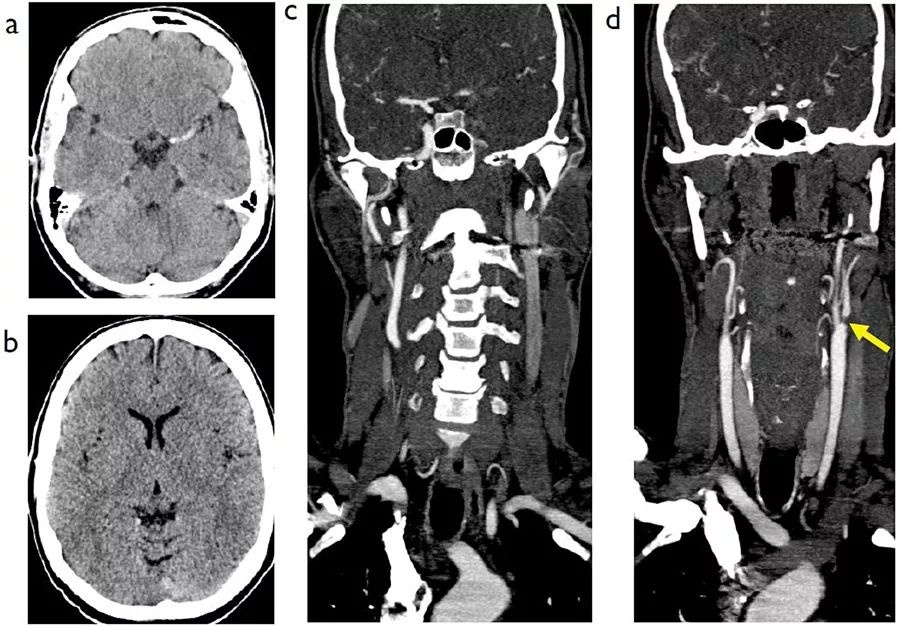

图7  病史不详,A~B:发病后2小时CT平扫;C~D:CT血管造影(CTA)冠状位重建

CT平扫中可见左侧大脑中动脉高密度征,同时基底节区灰白质界限模糊,岛叶和豆状核显示欠清。CTA确认了左侧颈总动脉和大脑中动脉M1段的闭塞,左颈动脉球和颈内动脉起始部位可见严重狭窄(图中箭头),这种血管狭窄需要在取栓术后进行血管成形术治疗。

图9  另一例左侧大脑半球短暂性脑缺血发作患者,A:斜矢状位;B:斜冠状位

本例患者的左颈动脉区域可见串联状病变,左颈内动脉起始处有密集的钙化斑块,造成血管的严重狭窄,同时左侧颈总动脉也可见严重狭窄(图中箭头)。不过,超声扫描并未检出左颈总动脉的病变。这种在血管分叉处密集的不规则斑块钙化会使测量精确的管腔尺寸变得更困难。